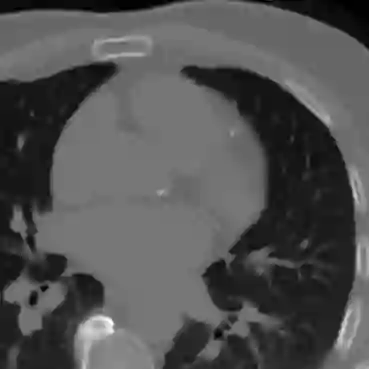

Coronary artery disease (CAD), one of the leading causes of mortality worldwide, necessitates effective risk assessment strategies, with coronary artery calcium (CAC) scoring via computed tomography (CT) being a key method for prevention. Traditional methods, primarily based on UNET architectures implemented on pre-built models, face challenges like the scarcity of annotated CT scans containing CAC and imbalanced datasets, leading to reduced performance in segmentation and scoring tasks. In this study, we address these limitations by incorporating the self-supervised learning (SSL) technique of DINO (self-distillation with no labels), which trains without requiring CAC-specific annotations, enhancing its robustness in generating distinct features. The DINO-LG model, which leverages label guidance to focus on calcified areas, achieves significant improvements, with a sensitivity of 89% and specificity of 90% for detecting CAC-containing CT slices, compared to the standard DINO model's sensitivity of 79% and specificity of 77%. Additionally, false-negative and false-positive rates are reduced by 49% and 59%, respectively, instilling greater confidence in clinicians when ruling out calcification in low-risk patients and minimizing unnecessary imaging reviews by radiologists. Further, CAC scoring and segmentation tasks are conducted using a basic UNET architecture, applied specifically to CT slices identified by the DINO-LG model as containing calcified areas. This targeted approach enhances CAC scoring accuracy by feeding the UNET model with relevant slices, significantly improving diagnostic precision, reducing both false positives and false negatives, and ultimately lowering overall healthcare costs by minimizing unnecessary tests and treatments, presenting a valuable advancement in CAD risk assessment.